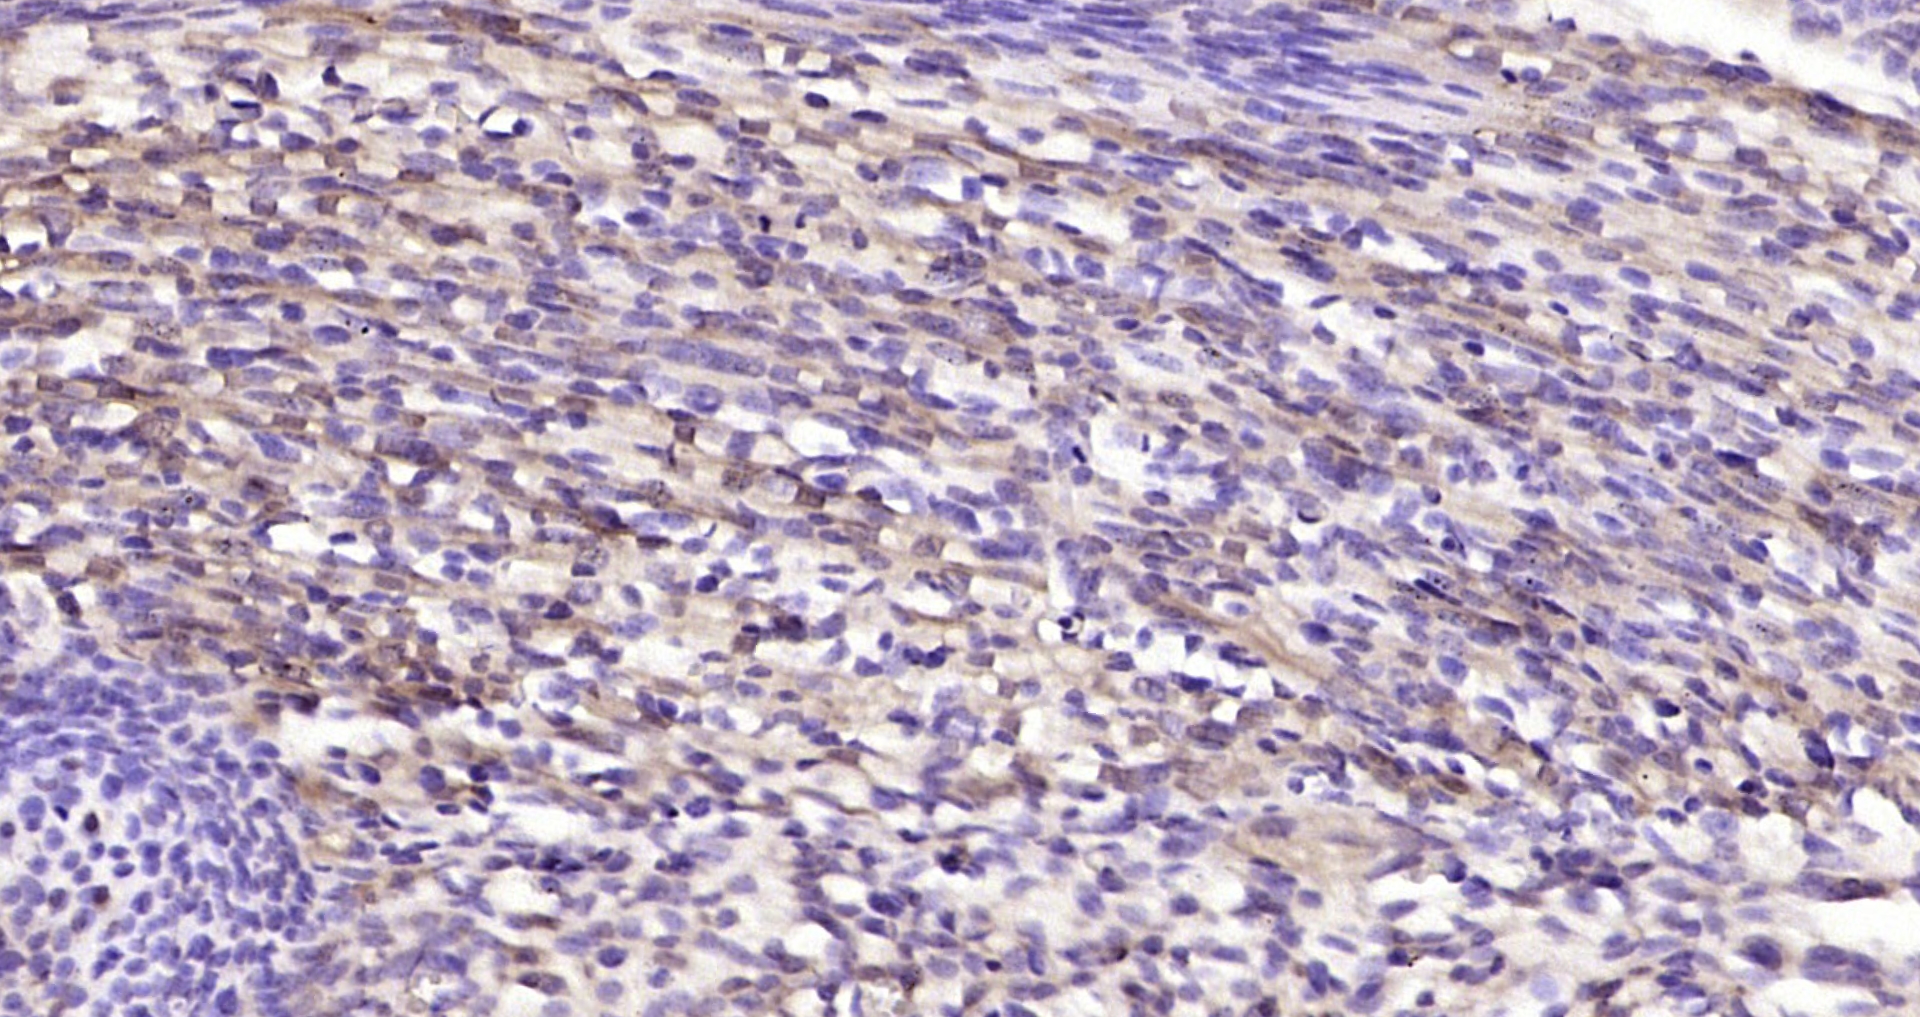

Immunohistochemical staining of human tonsil shows strong cytoplasmic and nuclear positivity in reaction center cells.